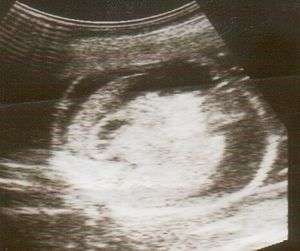

| An ultrasound featuring a fetus with Hydrops fetalis | |

Hydrops fetalis can be diagnosed and monitored by ultrasound scans. Prenatal ultrasound scanning enables early recognition of hydrops fetalis and has been enhanced with the introduction of MCA Doppler.